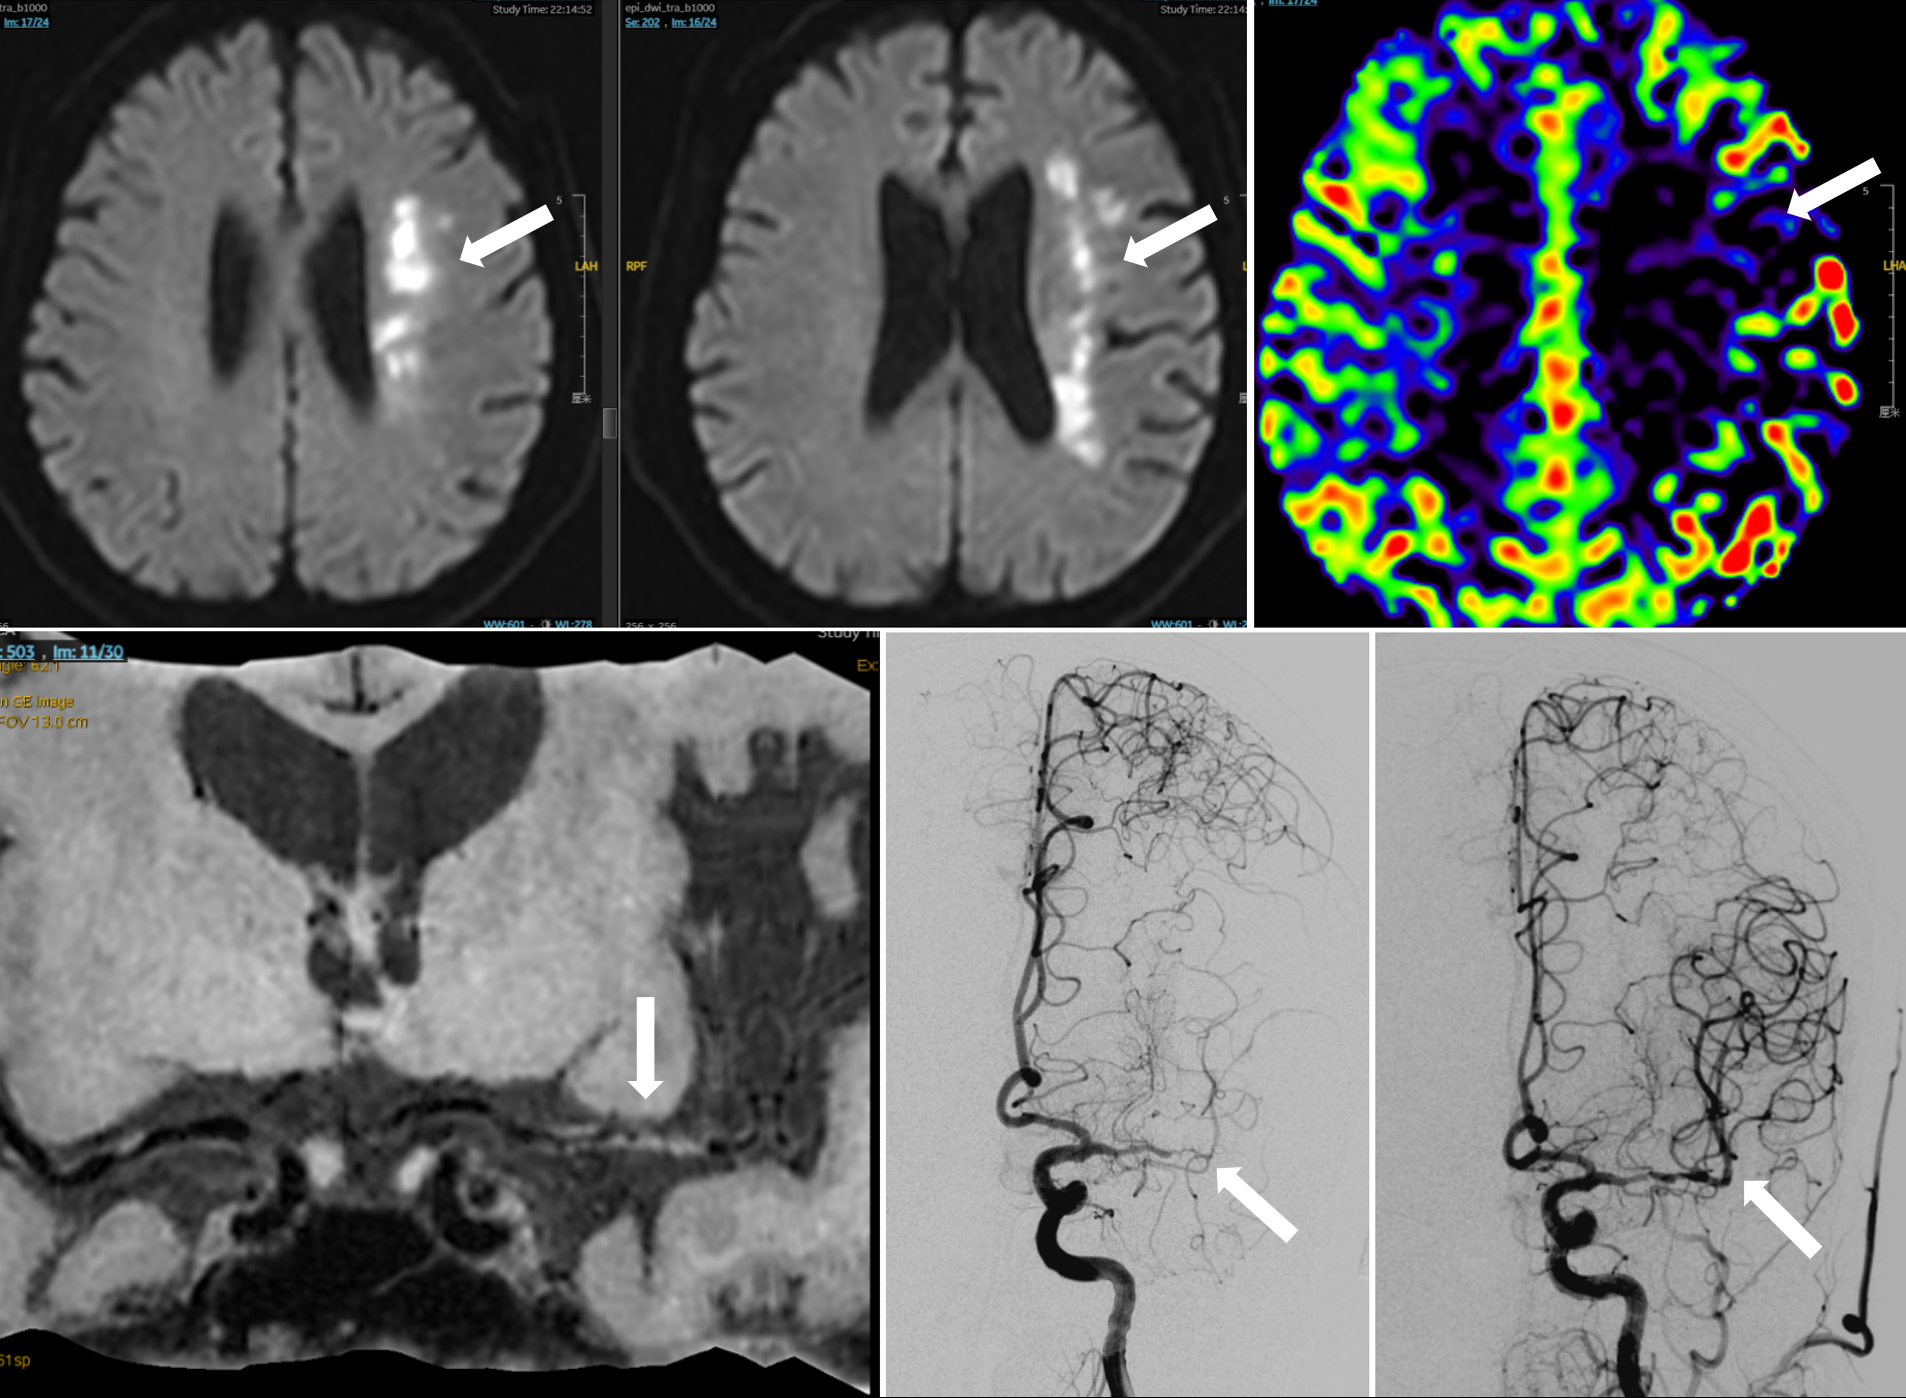

如图可见左侧基地动脉汇合椎动脉处重度狭窄,病变处为短节段斑块。术后通过支架治疗脑血管完全恢复。

对于脑梗死患者而言,如果在采取最优化药物治疗后,仍存在梗死风险,全麻下的支架治疗则成为了一种有效的治疗选择。特别是对于极重度狭窄病变,手术难度更是呈几何倍数增加。在这类手术中,医生首先需要在复杂的血管结构中寻找真实管腔,这犹如在迷宫中寻找出口,需要医生具备丰富的经验和敏锐的观察力。找到管腔后,再小心翼翼地进行球囊扩张,开辟出一条通道,这个过程就像是在薄冰上行走,稍有不慎就会引发严重后果。只有在通道成功开辟后,才能植入支架,打开血液流通的“隧道”。整个过程是在亚毫米级的精度下进行的,每一个操作都需要术者具备成熟的操作技术和冷静的判断能力,任何一个微小的失误都可能导致手术失败,给患者带来不可挽回的损失。